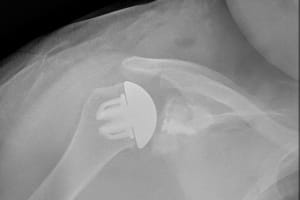

AFTER:

This is an x-ray after surgery demonstrating a "stemless" shoulder replacement.